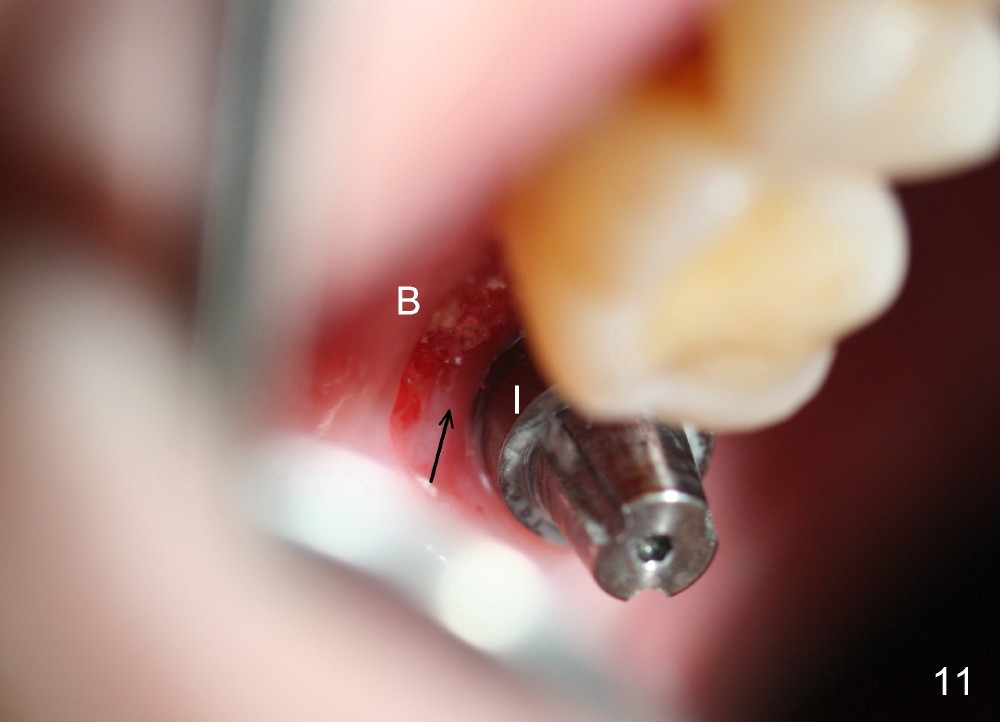

The patient returns to clinic 1 month postop, because of loosening of the provisional. The buccal socket appears to have epithelium (Fig.11 B); the keratinized gingiva has apparently moved (arrow) to cover the buccal surface of the implant (I). The long abutment, which was used for retention of the immediate provisional as well as the graft and collagen dressing, has finished its mission. It is changed to a shorter one to accommodate the future occlusion. A second implant is planned to be placed at the site of #31.